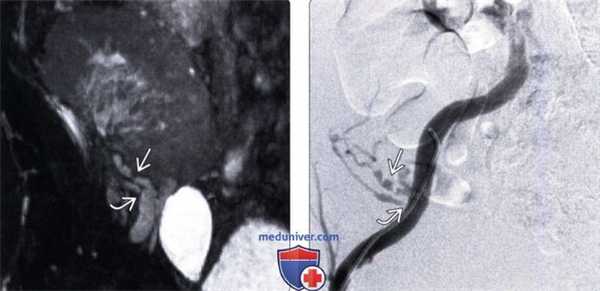

(Левый) Фронтальный срез при МРА без контрастирования, выполненной при подозрении на стеноз почечной артерии поданным допплерографии у пациента с отсроченной функцией трансплантата и гипертензией, развившейся через три месяца после трансплантации от умершего донора. Визуализируется две почечные артерии с выраженным стенозом в устье нижней артерии и диффузной неровностью контуров в верхней артерии .

(Правый) При цифровой субтракционной ангиографии у этого же пациента подтверждено диффузное поражение верхней артерии с чередованием стенозов и расширений, а также более локализованный стеноз нижней артерии.